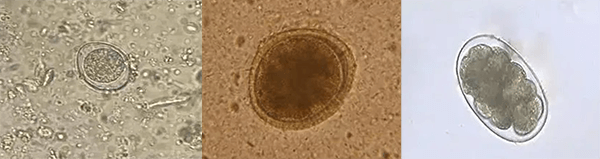

·à±ã¼ÄÉú³æ¼ì²é

ΪSDÌṩ¶¯Îï¼ÄÉú³æÌå¼ìɸ²é¡¢²¿·ÖÌåÍâÈÜѪʵÑéÈ·ÈÏ¡¢ÑªÒºÏ¸°ûÆÊÎöÒǾµ¼ì¸´ºË¼°ÖÖÖÖÊô¶¯Îï¹ÇËèÓкËϸ°ûÔöÉúˮƽ¼°¶¾ÐÔת±äÌṩ²Î¿¼¡£